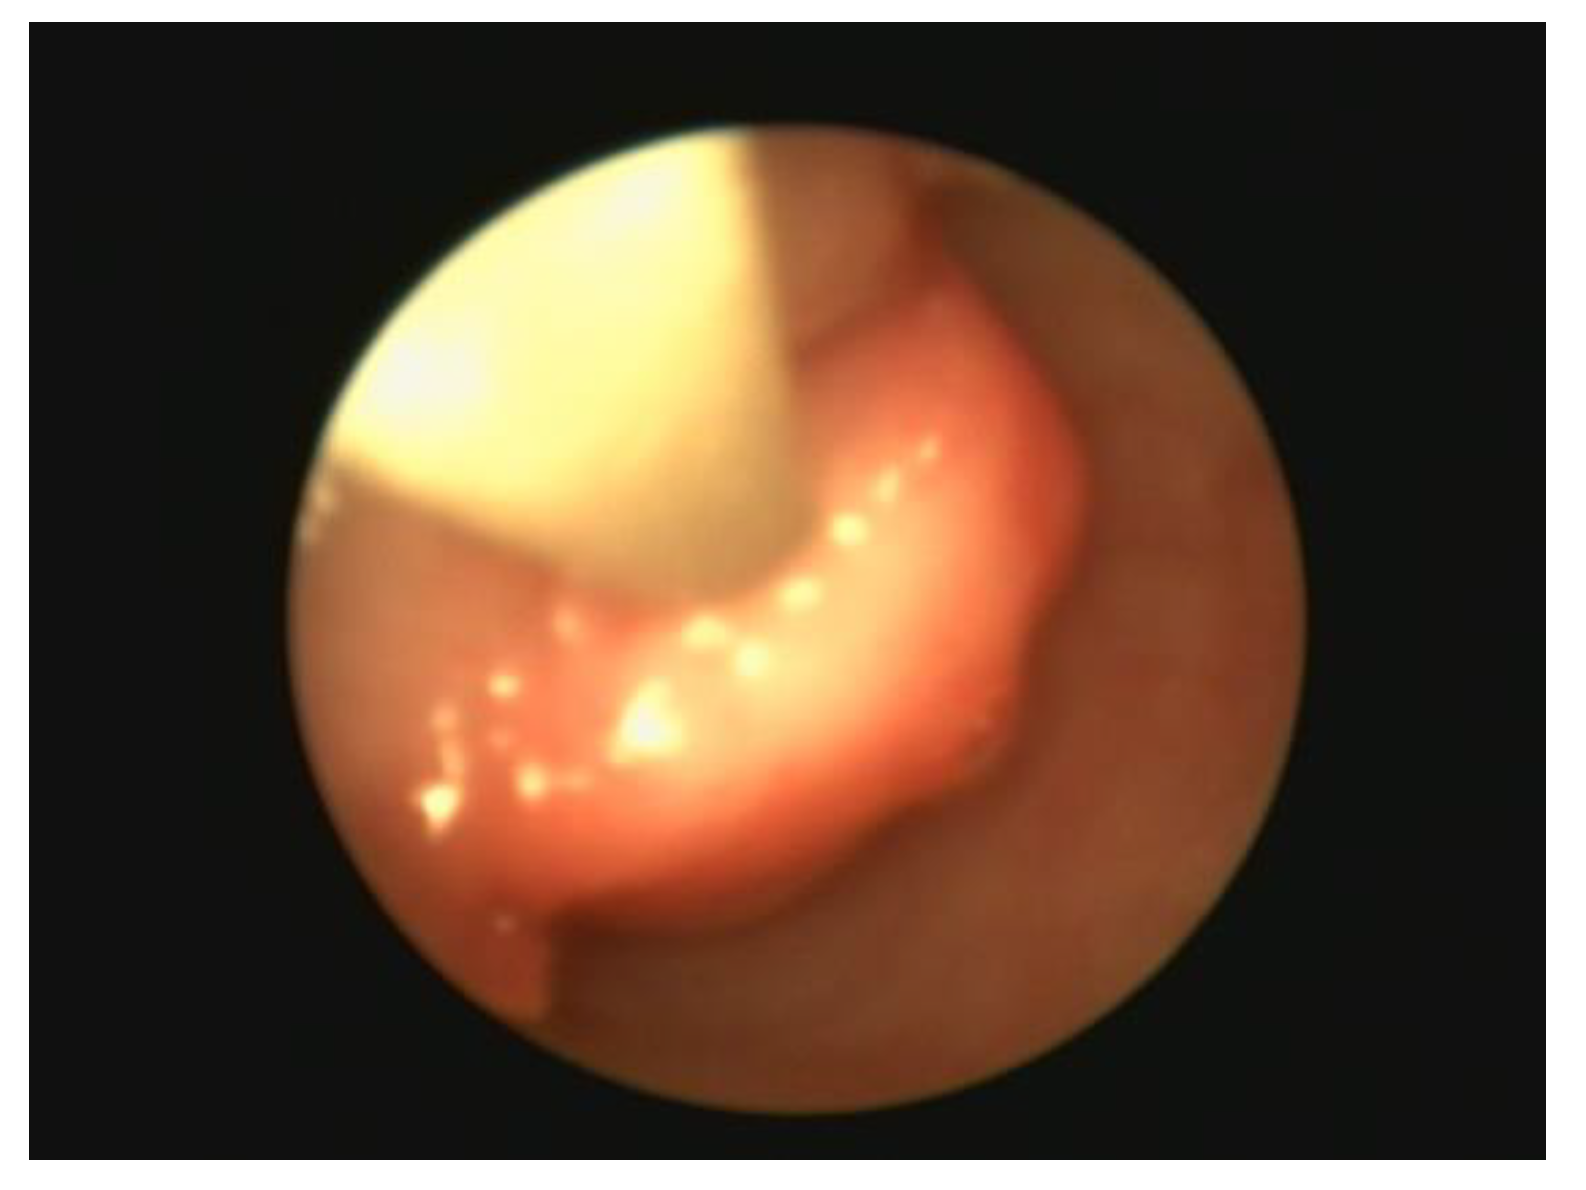

Regular evaluation of the bitch throughout the oestrous cycle is essential for determining the optimal days for mating or insemination with fresh, refrigerated, or frozen sperm. Vaginoscopy can aid in timing ovulation by assessing changes in the form, colour, and secretions of the mucosa, which correlate with hormonal variations, particularly during proestrus and estrus when the appearance of the vaginal mucosa and cervix changes (Figure 8).

Figure 8. Endoscopic view of the vagina during early to mid estrus at a Labrador female dog.